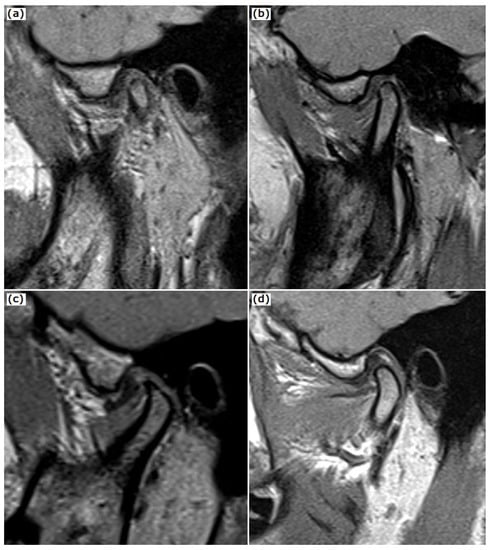

2.1. MRI Examination